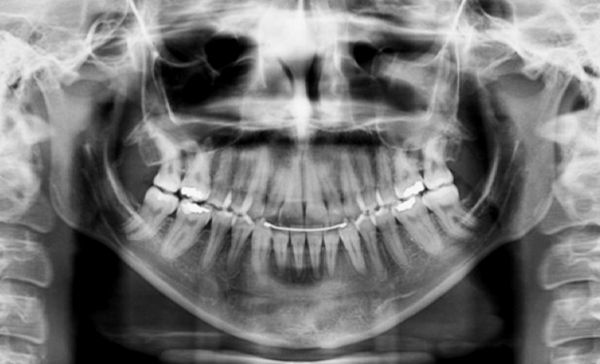

Radiografia final